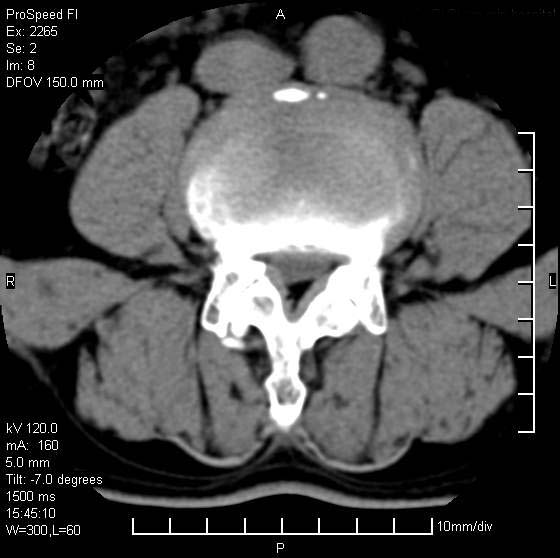

以下是引用qiushi在2007-8-22 17:26:00的发言:[br]没骨窗![br] 1、 l5~s1间盘膨出伴轻度突出(中央型)、变性。[br] 2、l4~5间盘膨出伴突出(右侧远外侧型)。[br] 3、l3~4间盘膨出。[br] 4、腰椎退行性变。[br]

以下是引用随缘的人在2007-8-22 20:56:00的发言:[br]腰椎退行性变:1。l4/5,l5/s1膨出[br] 2。l5/s1间盘退行性变 [br] 3。腰椎骨质增生

以下是引用liaizhi在2007-8-22 22:13:00的发言:[br]1,l4-5锥间盘膨出,2,l5-s1椎间盘膨出并退变(椎间盘呈真空征);3,血管瘤(椎体骨小梁稀疏粗大)?